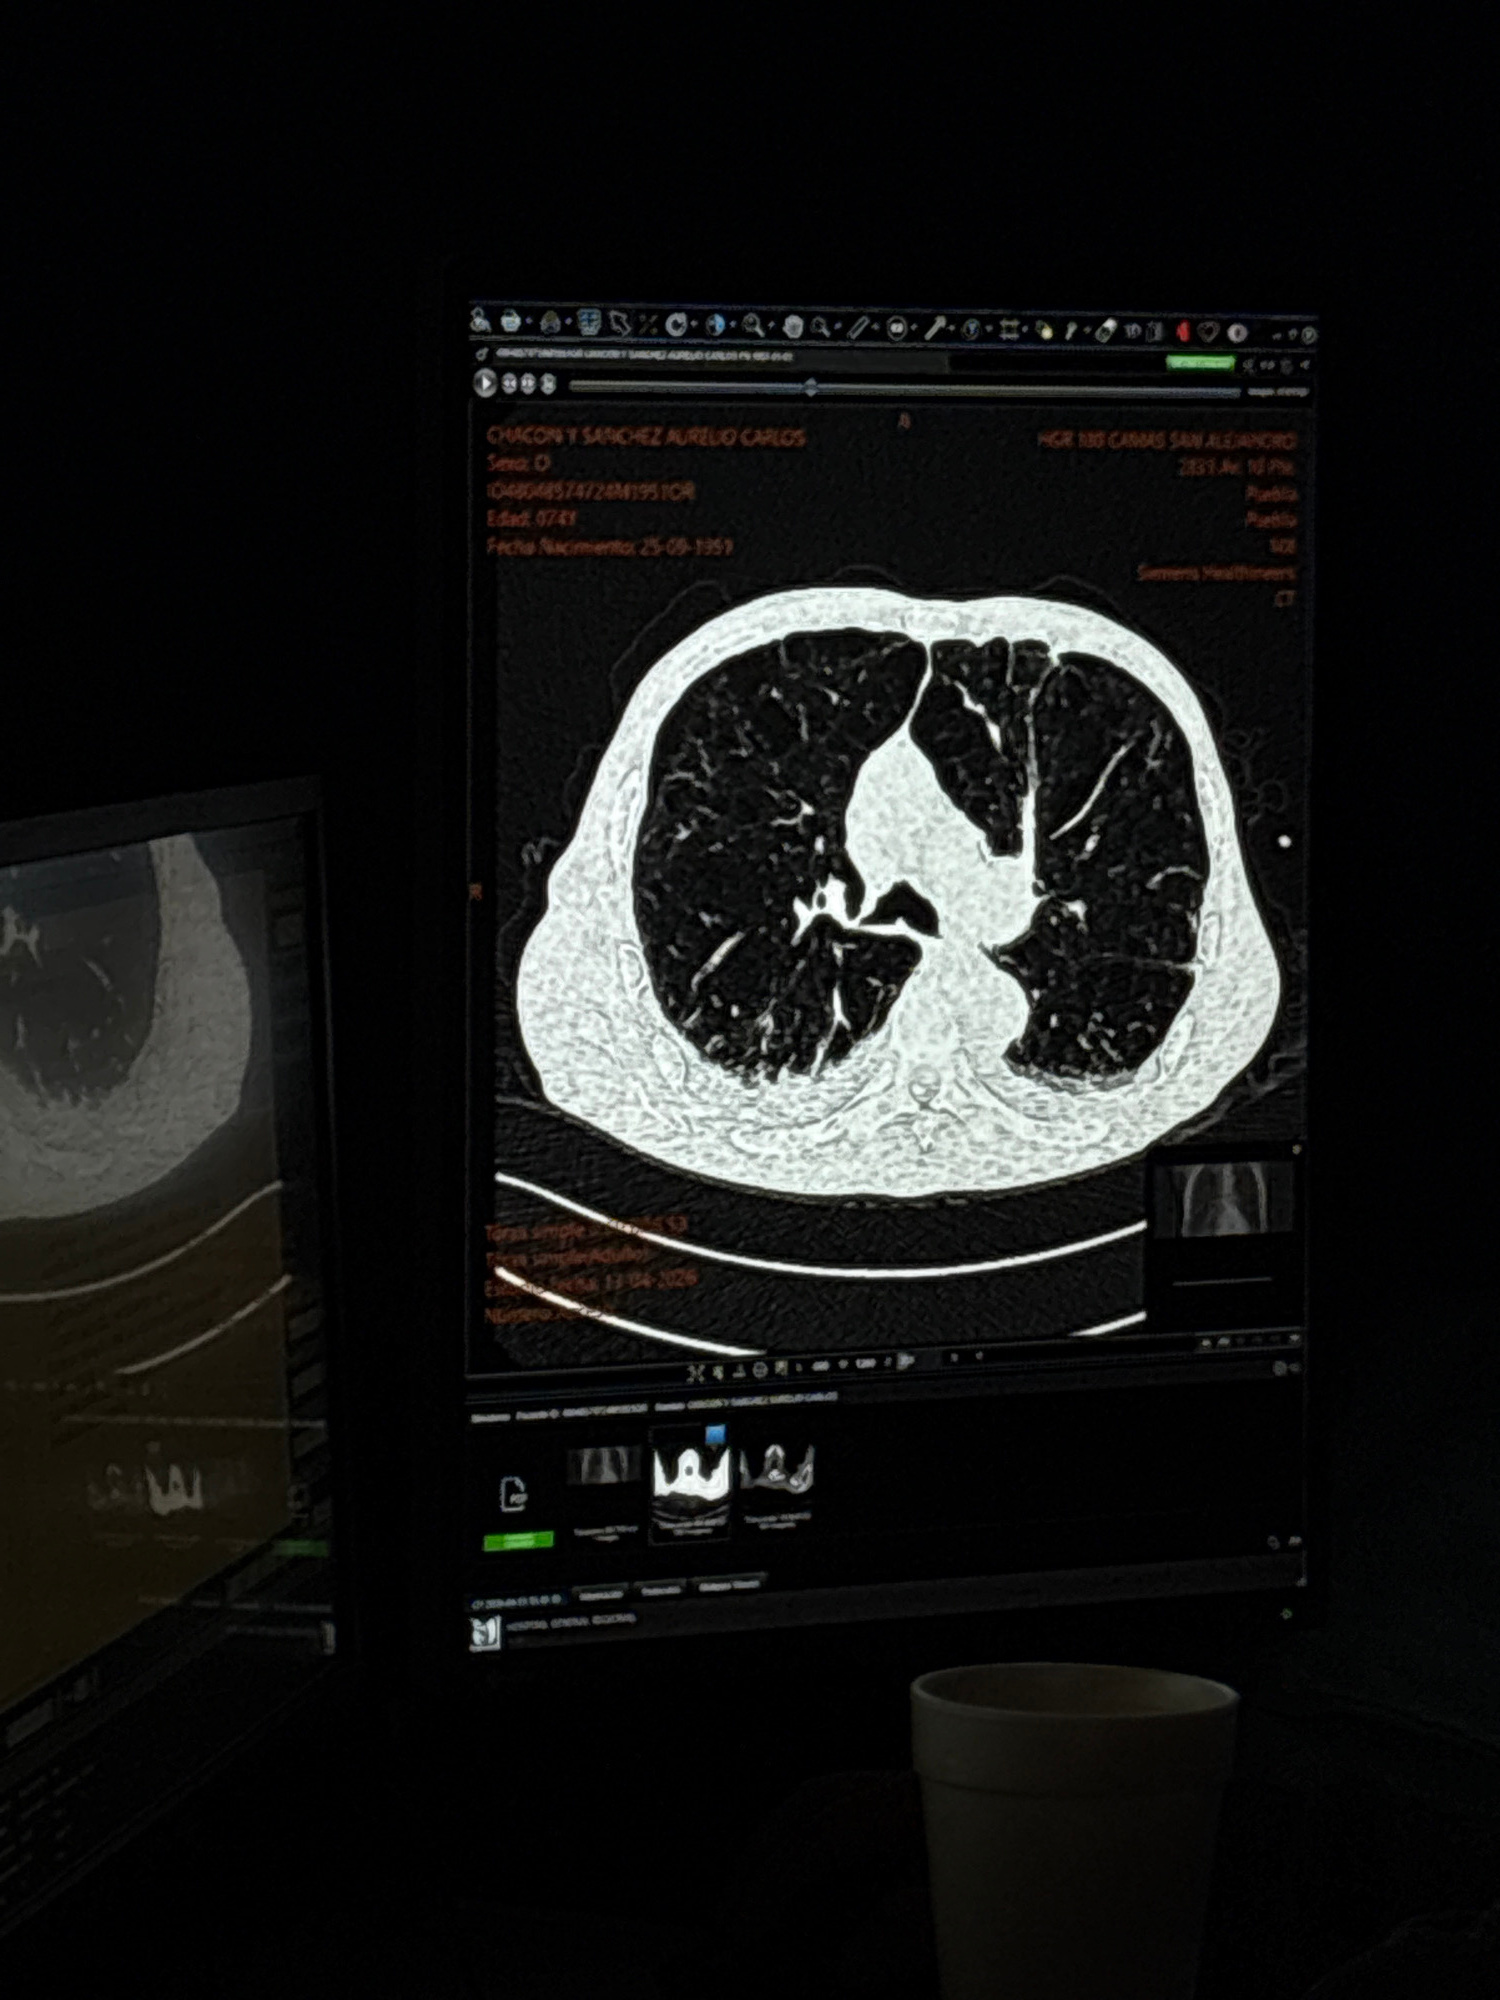

The image shows a CT scan of a lung displayed on a computer monitor. The scan shows the lung's internal structures in detail. The computer monitor also displays patient information, including the pati…read more